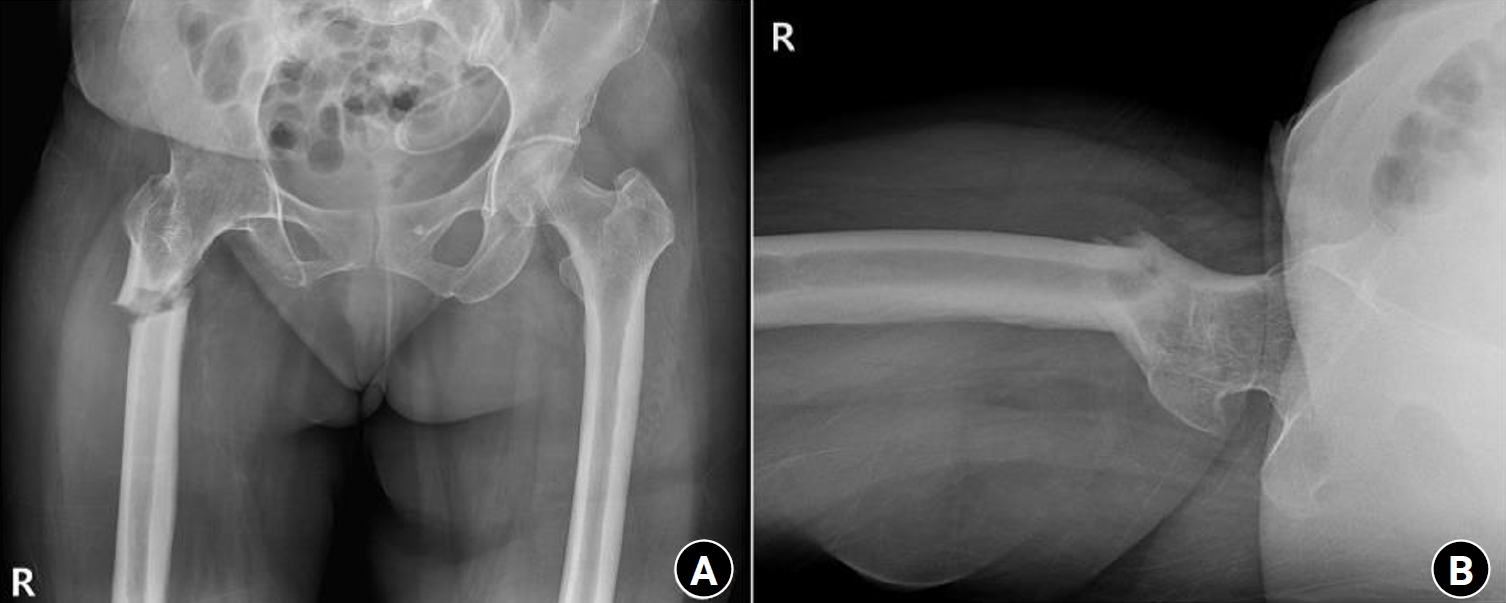

Fig. 5.

Radiographs of the same patient with a proximal one-third fracture of the left femur. (A) Anteroposterior view. (B) Lateral view.

Case 2: osteogenesis imperfecta

An 8-year-old female patient visited our emergency room complaining of pain in the left thigh that began on the day of her visit. She slipped and directly injured her thigh upon falling to the left. Initial examination revealed normal laboratory findings, including serum calcium levels of 9.0 mg/dL and inorganic phosphorus levels of 4.7 mg/dL. Radiographic evaluations, including anteroposterior and lateral views of the left femur, demonstrated a transverse irregular fracture line in the proximal one-third area of the left femur, accompanied by lateral cortex hypertrophy. Importantly, the possibility of malignancy or infection as contributing factors to the fracture was considered low. Two years prior, the patient had visited the pediatric department of our hospital due to concerns about her height, which was below that of her peers. Following genetic testing, she was diagnosed with osteogenesis imperfecta and has since been monitored by both the pediatrics and orthopedics departments. At that time, lateral bowing of both femurs was observed in both lower extremities during standing anteroposterior evaluations (Figs. 4, 5). She had previously undergone epiphysiodesis on both femurs due to genu valgum. After diagnosis, the patient underwent open reduction and internal fixation using an ender nail. Follow-up evaluations indicated successful bone union at the fracture site.